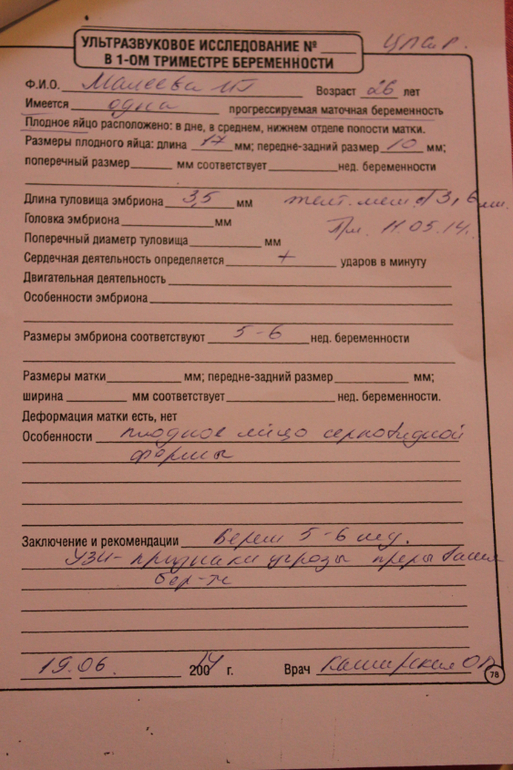

Так вот. Мы в матке! И мы 3,5 мм! Такие маленькие:))) Сердечко бьется, все отлично.

Кладут на сохранение на недельку, отдохнуть от работы, и чтобы мы хорошенько прикрепились.  Так что, с завтрашнего дня на больничном в стационаре поваляюсь, а то давно в отпуск хочу, я и рада была предложению лечь отдохнуть:)